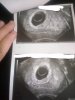

Ja mialam tez taka sytuacje ale okazało się że to nie cialko zolte a jedynie jakas czesc pecherzyka. Zaraz poszukam zdjęcia i wstawię. Lekarze myśleli że to pecherzyk zoltkowy a jednak nie. Za każdym razem od lekarzy slyszalam ze jesli jest pecherzyk bedzie tez zarodek.

Załączniki

• received_743885783008413.jpeg

received_743885783008413.jpeg

136,4 KB · Wyświetleń: 85